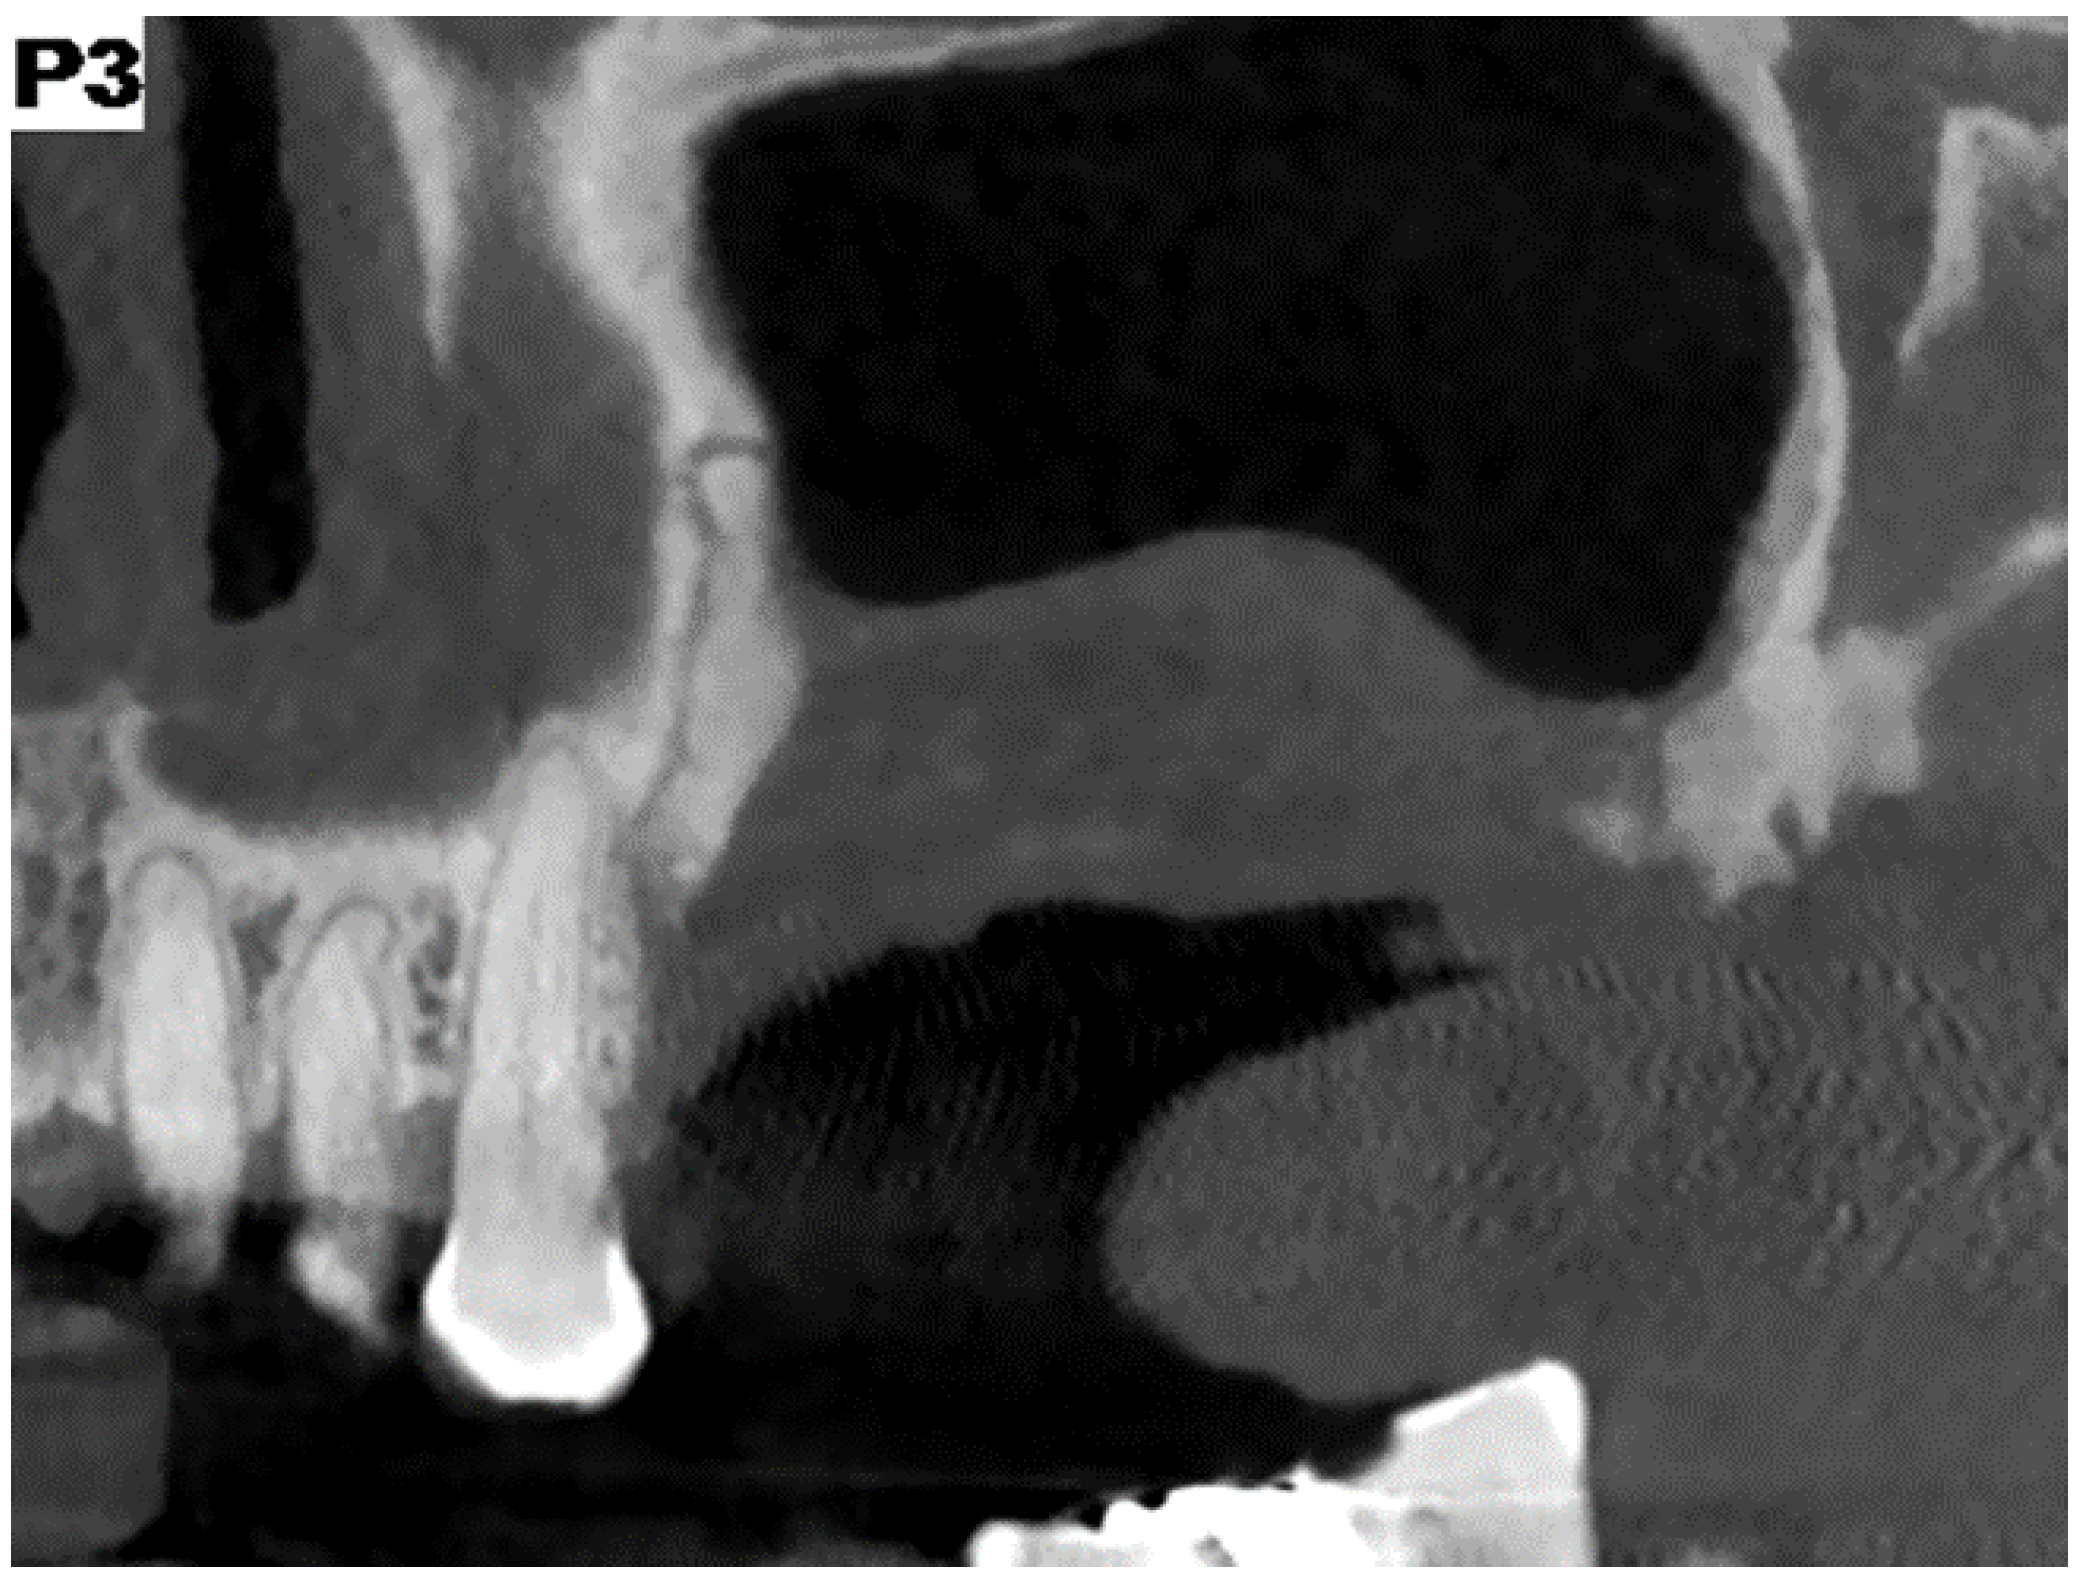

Figure 12. CBCT view at one year.

After 12 months, the control CTs were performed (Figure 1, Figure 2, Figure 3, Figure 4, Figure 5, Figure 6, Figure 7, Figure 8, Figure 9, Figure 10, Figure 11 and Figure 12).

After 12 months, the control CT scans were performed confirming the resolution of the disease; no symptoms were detected.